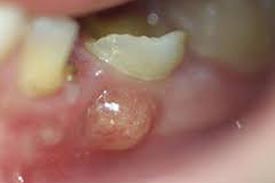

▲サホライドを塗って黒くなった様子

▲乳歯のエナメル質から象牙質への虫歯の進行の抑制率